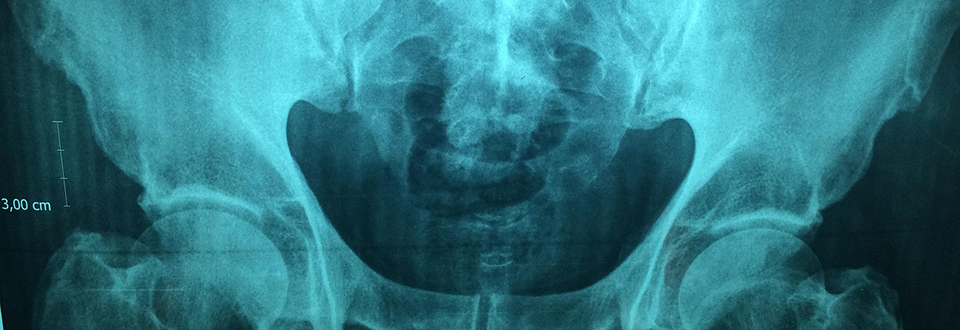

“Ad esempio, studi in vitro con cellule di tessuto osseo hanno dimostrato che le microplastiche compromettono la vitalità cellulare, accelerano l’invecchiamento cellulare e alterano la differenziazione cellulare, oltre a promuovere l’infiammazione”, spiega Oliveira. Il ricercatore riferisce che studi sugli animali hanno scoperto che la senescenza accelerata degli osteoclasti può compromettere la microstruttura ossea, causando displasia. Ciò può portare a indebolimento osseo, deformità e fratture potenzialmente patologiche.

Oliveira spiega inoltre che, sebbene gli effetti di queste particelle sulla meccanica ossea non siano ancora del tutto compresi, i dati suggeriscono che la presenza del materiale nel flusso sanguigno, ad esempio, possa compromettere la salute delle ossa. “Ancora più sorprendentemente, un significativo corpus di ricerche suggerisce che le microplastiche possono raggiungere profondità nel tessuto osseo, come il midollo osseo, e potenzialmente causare disturbi nel suo metabolismo”, conclude Oliveira.